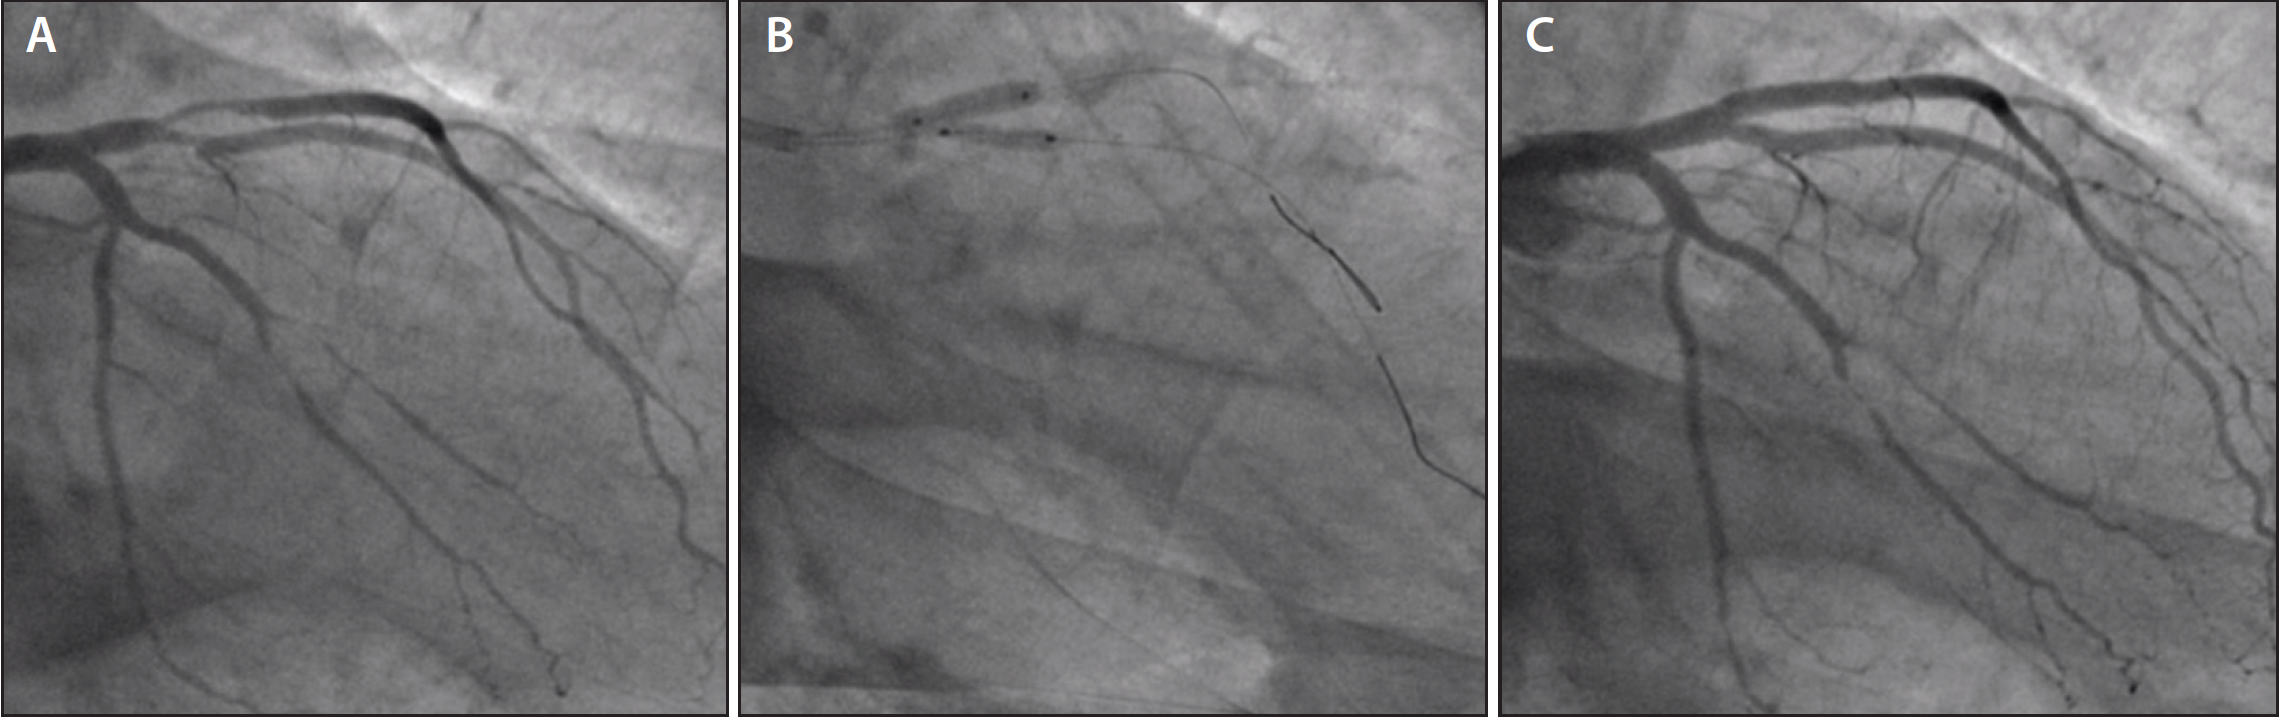

Figure 4. Bifurcation treatment with the A-BVS, two-scaffold strategy: bifurcation lesion of the left anterior descending artery and diagonal artery (Medina classification 1,1,1) (A); A-BVS in the left anterior descending artery main branch and A-BVS in D1 by TAP technique followed by snuggle balloon dilatation of scaffolds in the left anterior descending and diagonal arteries (B); good final result of two-scaffold strategy by TAP technique (C).